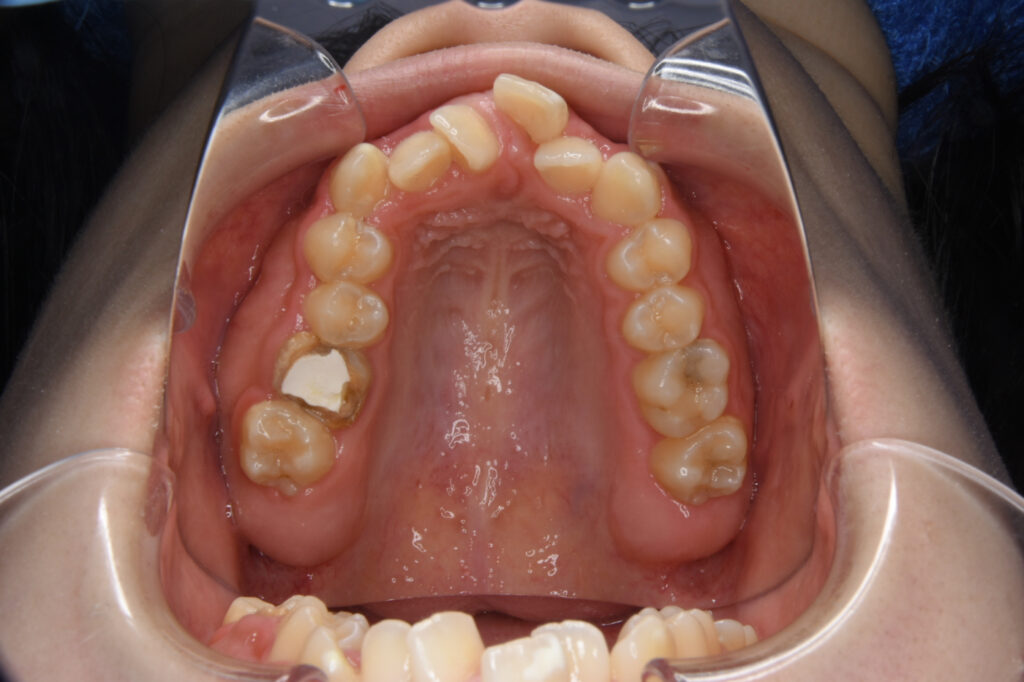

After

After

After

After

| 年齢 | 20代 |

| 治療の内容 | 上顎両側第一小臼歯を抜歯。上顎下顎ともに唇側ワイヤー矯正装置を装着。口蓋に歯科矯正用アンカースクリューを1本使用。 |

| 期間・回数 | 1年3ヶ月・15回 |

| 費用 | 約84万円+消費税 |